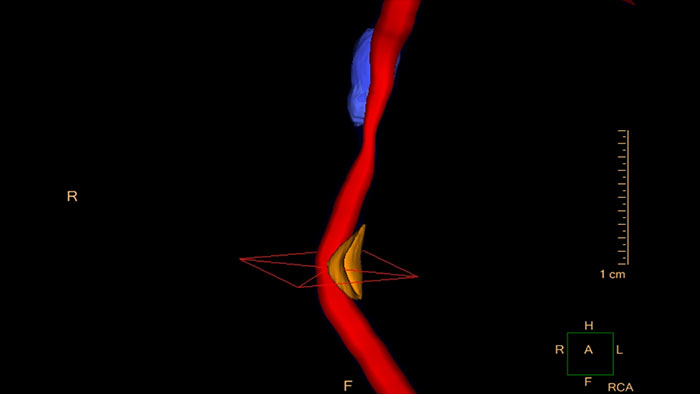

- Cardiac Plaque Assessment

-

CT Cardiac Plaque Assessment

Evaluate coronaries plaque

Enables performing cross-sectional measurements along the coronary arteries, and automatically calculates regional and global quantities of plaque volume.

Benefits

- Provides automatic color-coded visualization of plaque content areas on vessel cross-sectional images.

- The user has the ability to edit the automatic results.